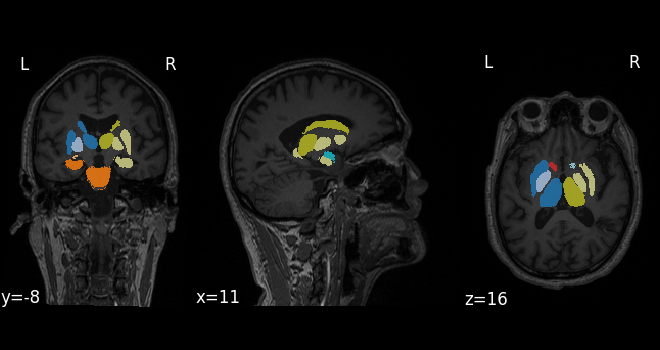

系统集成了高精度脑区分割算法,可自动识别一百多个脑结构,并计算各脑区在标准人群中的体积百分位位置,从而揭示个体的脑结构差异。在这些量化结果的基础上,Brain Visio 进一步实现了对帕金森病(PD)、阿尔茨海默病(AD)等神经退行性疾病的 AI 驱动风险评估、分期判断与病程进展预测。